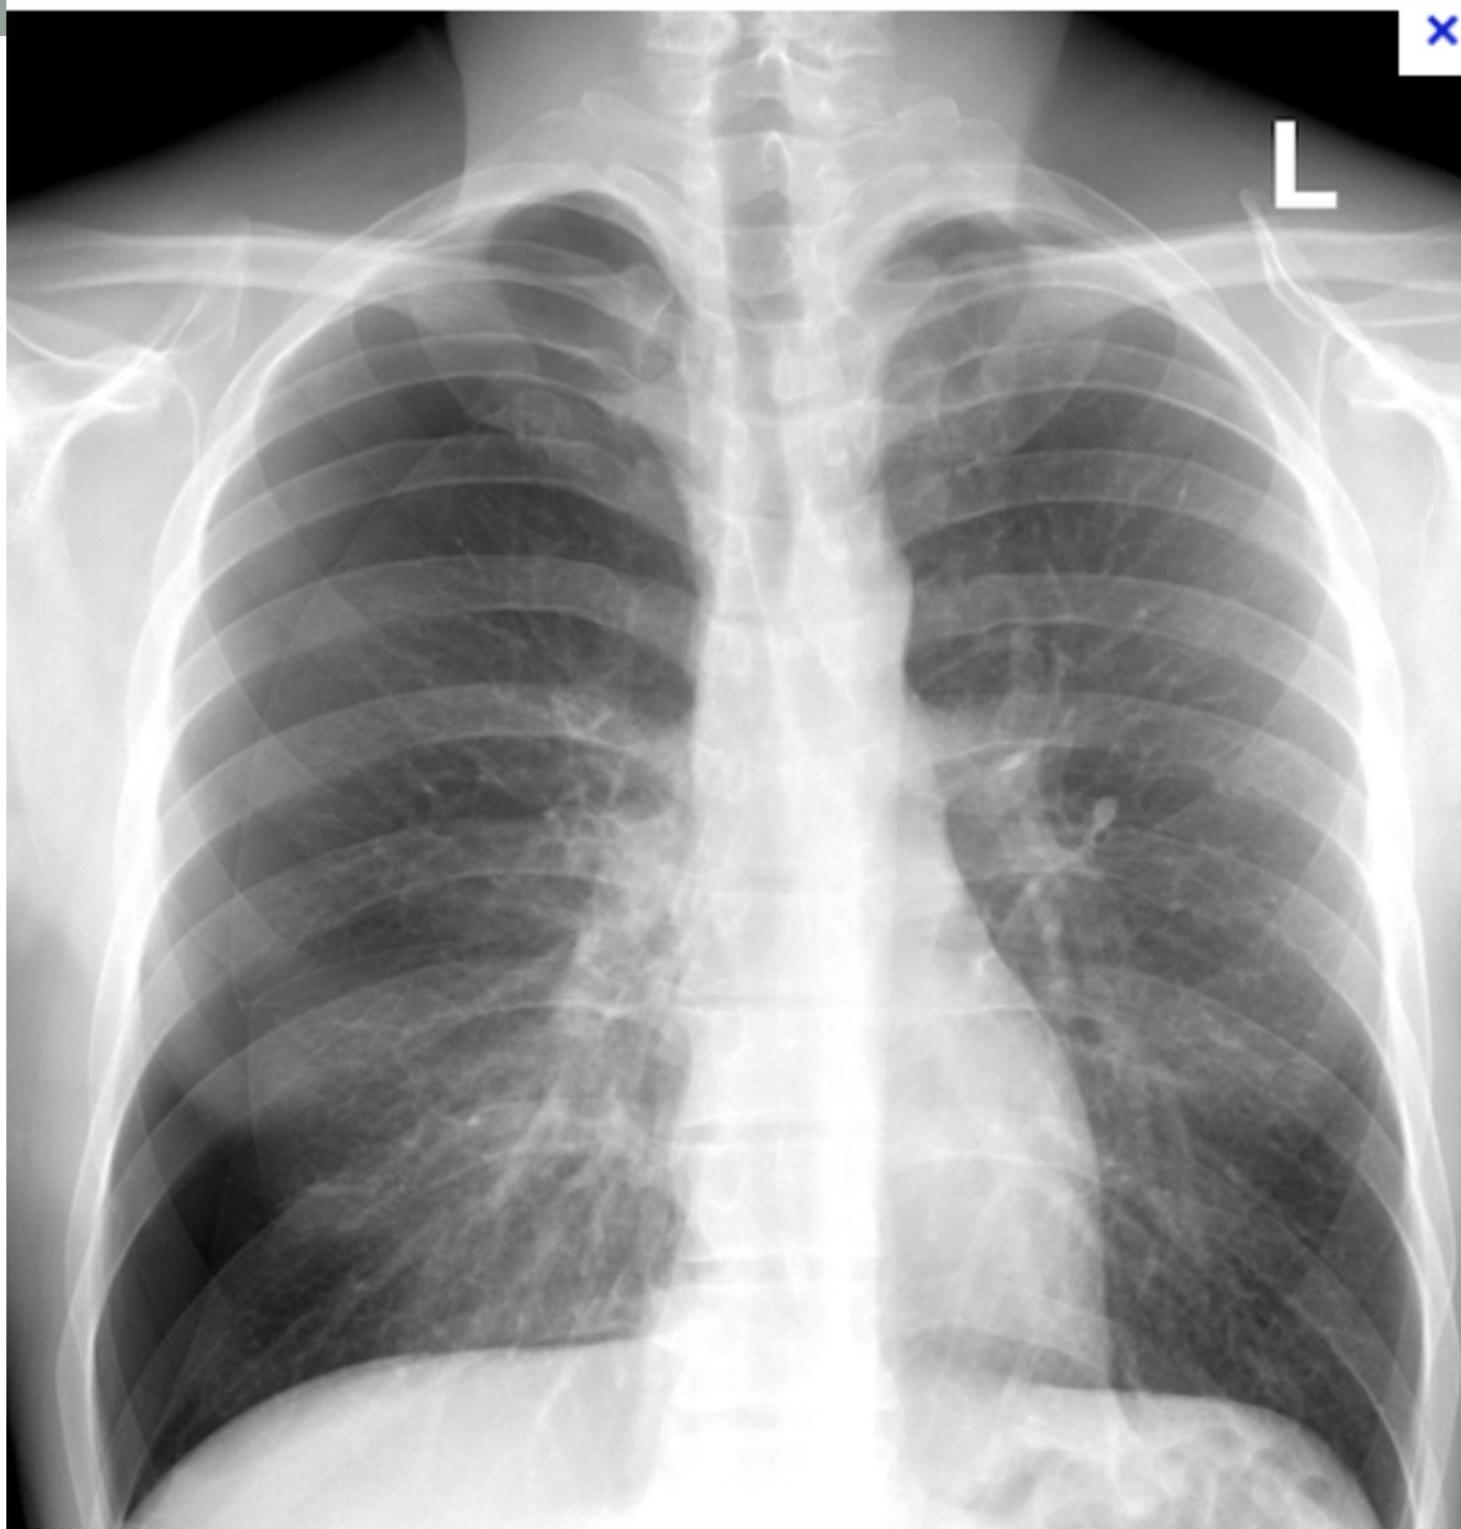

- CXR Findings:

- Westermark sign: Clarified area (hyperlucency) secondary to oligemia.

- Hampton sign: âDome stuffedâ (hump).

Case 5: Pneumothorax

- Presentation: 45M post-thoracentesis (1.5L removed). Develops sudden R-sided chest pain.

- Management:

- Stable < 3cm: Supplemental O2 and observation.

- Stable > 3cm: Needle aspiration.

- Failure or Unstable: Chest tube. if >3cm or failed aspiration or unstable patient